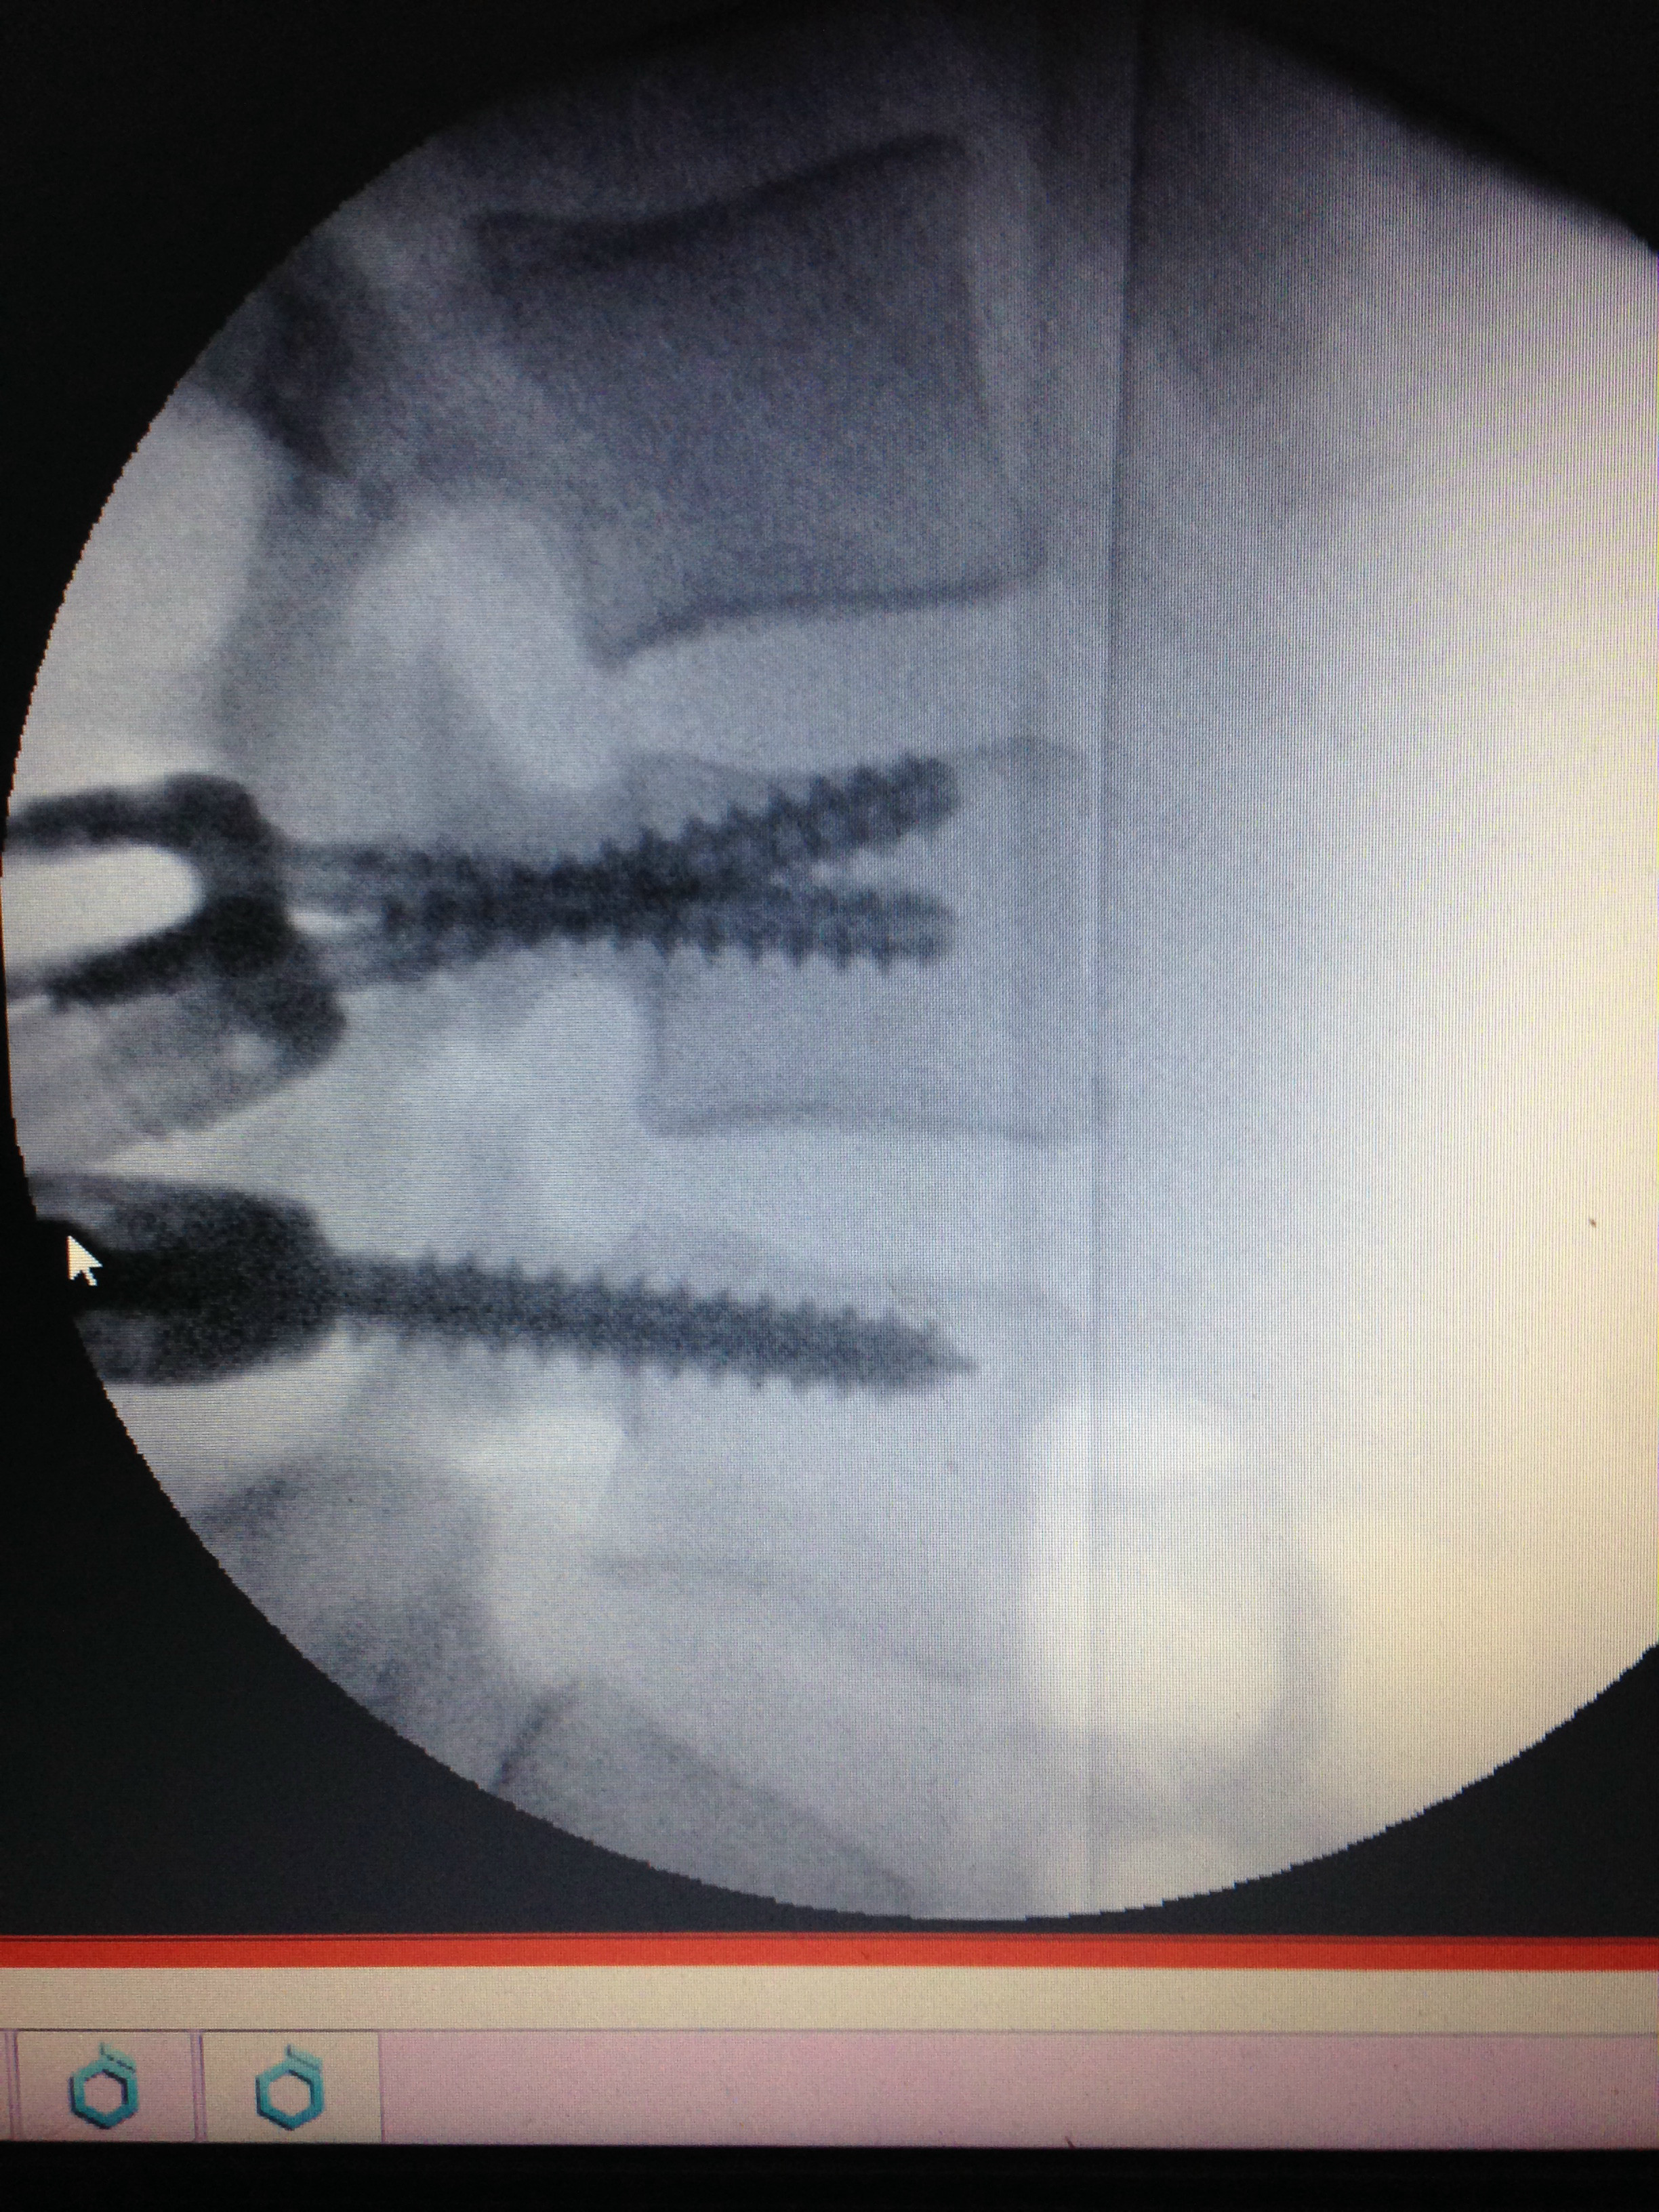

I demanded a CT scan and sure enough had two spinal breaks and the bone was swinging, so luckyily I did not become paralysed. They gave me a spinal fusion l3-4 with bone marrow, rods and screws. Six months later I learned how to walk again. I was gradually growing strong again, although I suffered left leg numbness post op, which never returned. I started Physio 10 months later and decided to travel as I felt I'd missed out.

My fiancé and I set off, but I had a fall in Calpe. I took myself to the hospital as my left foot went blue. That was April last year 2016 and I have slowly deteriorated since then. I told my surgeon I could still feel the bone moving in my spine, and he suggested to take the metal out. I demanded another scan, and it showed the fusion hadn't been successful, so taking the metal out wasn't an option.